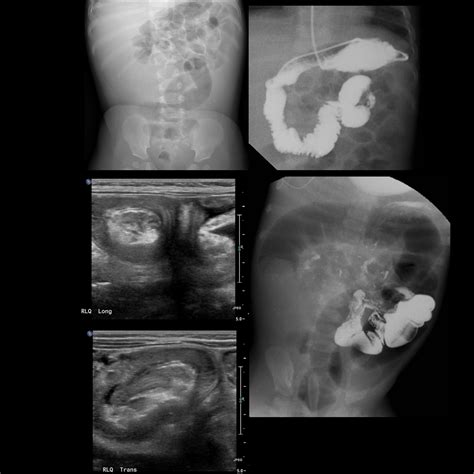

Furthermore, the ligament is of particular interest in the study of malrotation. If the ligament is absent or improperly positioned, the small intestine may not fixate correctly, leading to a condition called midgut malrotation. This can result in a volvulus, a dangerous twisting of the bowel that requires immediate emergency surgical intervention.

Radiologists rely on the Ligament of Treitz when interpreting imaging studies such as CT scans or fluoroscopy (barium swallow/meal). The position of the duodenojejunal flexure in relation to the vertebral column and the midline can provide diagnostic clues for anatomical anomalies. For instance, in a normal anatomical presentation, the flexure should be to the left of the midline and at the level of the L1 or L2 vertebrae.

When imaging confirms that the flexure is located to the right of the midline, it is a hallmark sign of intestinal malrotation. Recognizing these signs early through imaging can prevent life-threatening complications, especially in pediatric patients who are born with congenital intestinal positioning issues.